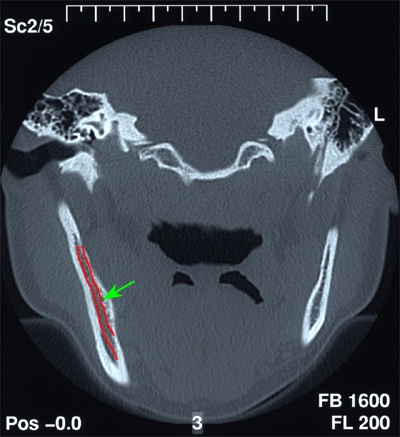

Die operativen Methoden erfordern, dass alle diese Probleme bei und in der Praxis unter erhöhten Hygienemassnahmen durchgeführt werden. Das Schwergewicht der allgemeinen zahnärztlichen chirurgischen Eingriffe liegt wohl in der Entfernung verlagerter Zähne, speziell der Weisheitszähne im Unterkiefer. Liegt der verlagerte Weisheitszahn so tief im Knochen, dass seine Wurzeln bis zum Teil an den Unterkieferrand reichen, lassen wir vorgängig der Operation ein sogenanntes CT (Computer-Tomogramm) erstellen, das uns die dritte, räumliche Dimension zum Verlauf der sensiblen Nerven im Unterkiefer zu den Wurzeln des Weisheitszahnes darstellt. Je nachdem, wo dieser Nerv verläuft, wird die Kraft zur Entfernung des Weisheitszahnes an verschiedenen Ansatzpunkten eingesetzt.

Abb. 1 zeigt das klinische Bild vor der Aufklappung. Der Pfeil markiert die Stelle, wo der Weisheitszahn unter der Schleimhaut im Knochen liegt. Vor der Operation musste ein CT zur transversalen Lagebeurteilung des sensiblen, wichtigen Lippennerves zur Wurzelspitze des Zahnes angefertigt werden. In der CT-Schichtaufnahme von Abb. 2 wird ersichtlich, dass der Weisheitszahn sehr tief unten liegt.